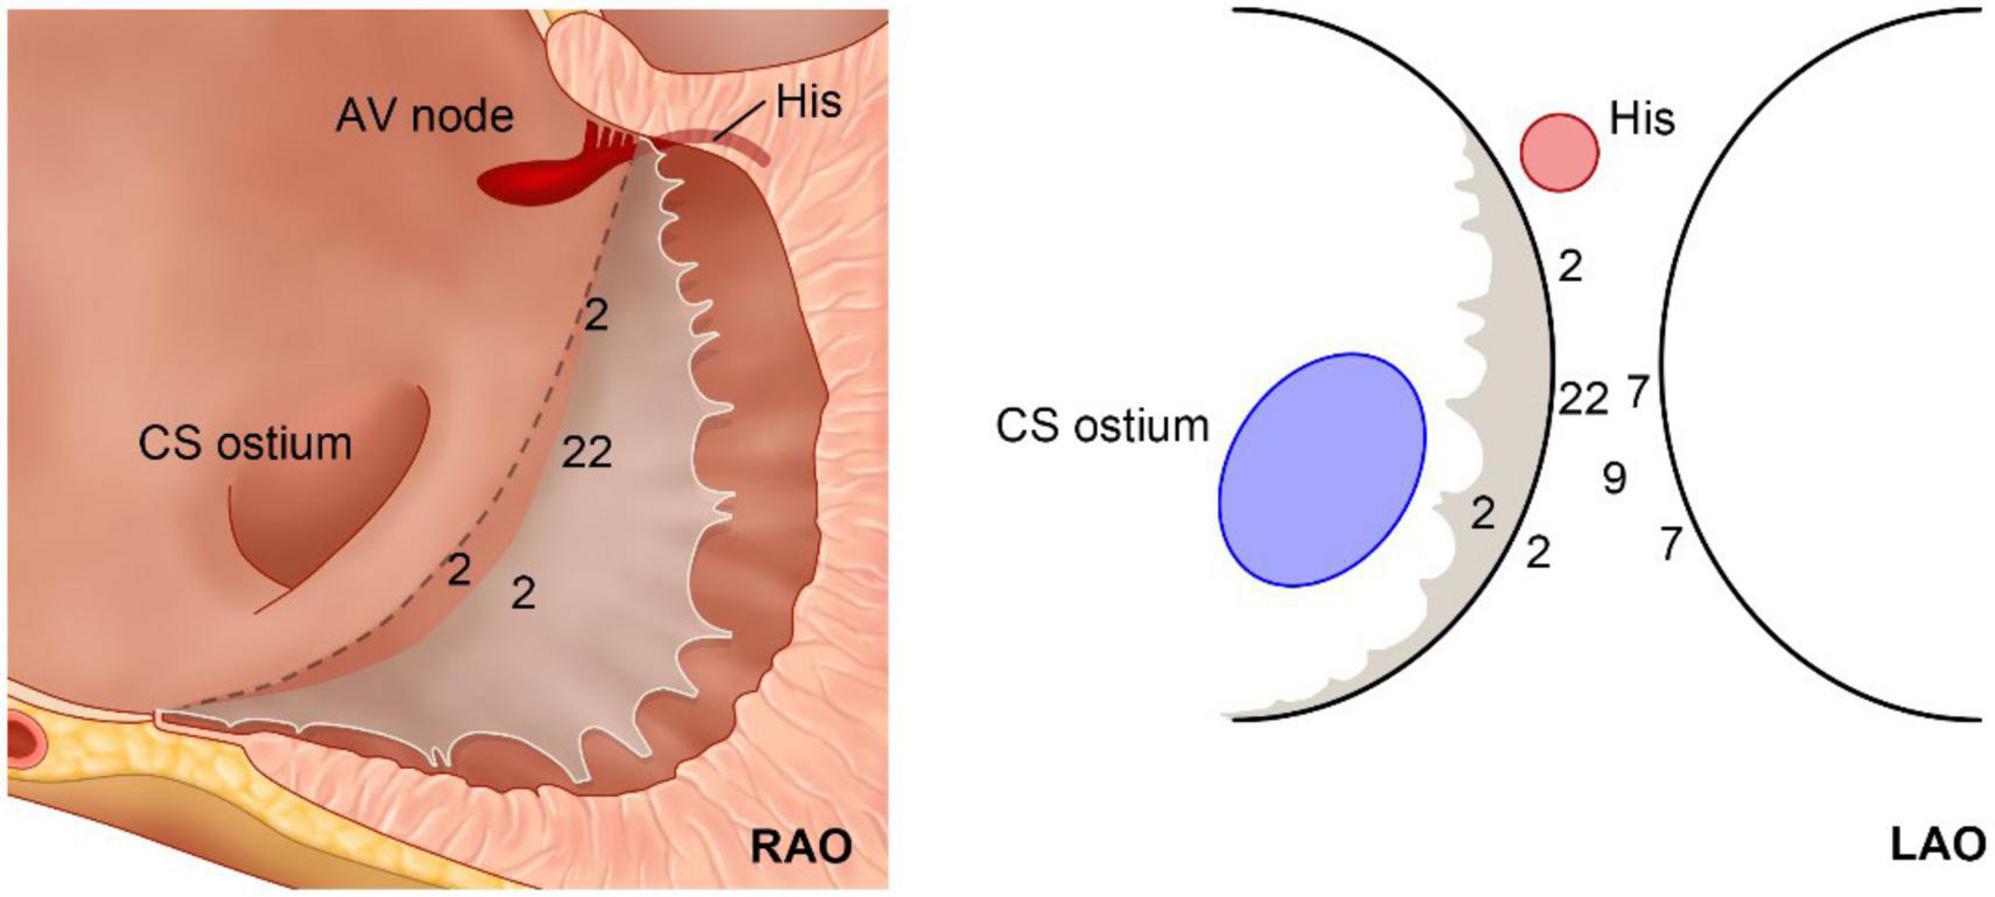

Ventricles were divided into 3 parts equally from the apex to base and the most basal part of the ventricle septum was considered as the basal septum. Moreover, the basal septum was defined as the area 2 cm away from the septal annulus, the upper boundary was the site of the left or right His, and the lower boundary was the borderline that separated from the septum. Those VAs with their earliest activation superior to the His point were not enrolled; as such, no patient was found to need ablation at the right coronary cusp.

The basal septum delineated in the present study could be considered a combination of the farthest left part of the tricuspid annulus and the basal inferoseptal aspect of the left ventricular wall, i.e., the posterior-superior process of the left ventricle (PSP-LV). In some recent studies, the latter was delineated as the “basal inferoseptal left ventricle” (9). Theoretically, this area could also be considered the farthest right portion of the mitral annulus; however, most studies did not delineate the VAs originating here as the “septal mitral annulus,” mostly because of the non-parallel position of the TA and MA. Based on the definition of the study, on the superior boundary of the basal septum lies the right fibrous trigone, and the inferior side was the upper end of the cardiac-crux area formed by the interventricular groove. Additionally, above this pyramidal structure lies the inferior wall of the right atrium, as well as the anteroinferior wall of the non-coronary cusp.

The complex anatomical arrangement has been translated into various VAs delineated by different groups. Hiroshi Tada et al. reported that the septum was the preferential site of origin for tricuspid annulus VAs (3). The latter has also been reported as the basal septum of the right ventricle for a distinct VA-originating structure by another group (10). Meanwhile, several studies have described the endocardial ablation of VAs from the left side, in which the structure was named “the basal infero-septal process of left ventricle” (7, 9), “left ventricular septum” (11), or “left ventricle adjacent to the membranous septum” (12). Additionally, the so-called basal infero-septal process has been successfully ablated from the atrial side (Figure 3) (13, 14).

In fact, these anatomical structures are very close to each other. Due to the neighboring topographic relationship, it is very difficult to differentiate these arrhythmias from each other before detailed mapping, and sometimes even attempted ablation. The tachycardias originating from these locations share several common ECG features, which have been shown in the present study. Almost all of the patients demonstrated an initial q or QS type wave at V1 with an abrupt reversal at V2, which has been identified as a sign of the septal accessory pathway in the ECG recognition of pre-excitation syndrome (2). Those patients eventually ablated from the right side demonstrated more QS type waves in V1; however, the QS type has little differential diagnosis value, as shown in Table 1. Nevertheless, if the ECG shows a more positive type (qR, R, RS), it is a predictive sign of warranting ablation from the left side. Additionally, the two groups demonstrated a significant difference but an obvious overlap in terms of the reversal lead.